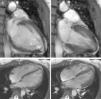

The CMRI revealed marked trabeculation in the apical segments of the LV with a diastolic ratio of noncompacted/compacted layers of 2.6, fulfilling CMRI criteria for noncompaction (Figures 2–4). LV mass was within normal limits and no delayed enhancement suggestive of fibrosis was detected after gadolinium administration.